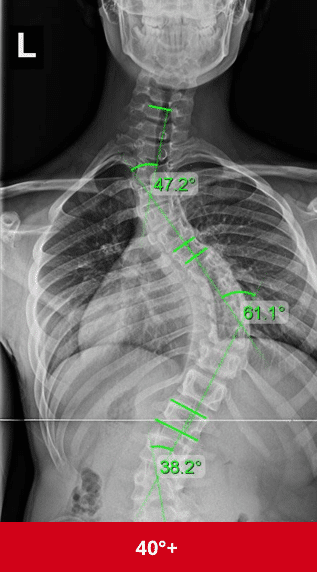

أسباب اعوجاج العمود الفقري مجهول السبب عند المراهقين وكيفية التشخيص المبكر يعاني العديد من المراهقين من اعوجاج العمود الفقري مجهول السبب (Adolescent Idiopathic Scoliosis – AIS)، وهو انحناء غير طبيعي في العمود الفقري دون

السبب الحقيقي وراء اعوجاج العمود الفقري عند المراهقين: نظرية جديدة تكشف ما لم تعرفه من قبل مقدمةيعاني بعض المراهقين من اعوجاج العمود الفقري مجهول السبب (Adolescent Idiopathic Scoliosis – AIS)، وهي حالة يتميز فيها